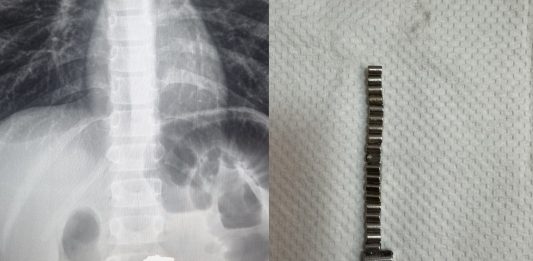

В Новосибирске 25 проглоченных магнитов проделали дыру в желудке ребенка

В Новосибирске ребёнка пришлось экстренно оперировать, чтобы извлечь из него 25 проглоченных магнитов. За то время, что они были внутри, у малыша образовались серьёзные осложнения, вплоть до дыры в желудке и свищей в кишечнике. Операция была проведена в экстренной хирургии Детской городской клинической больницы №1. В медучреждении рассказали, что в приемное отделение поступил ребенок с … Читать далее В Новосибирске 25 проглоченных магнитов проделали дыру в желудке ребенка